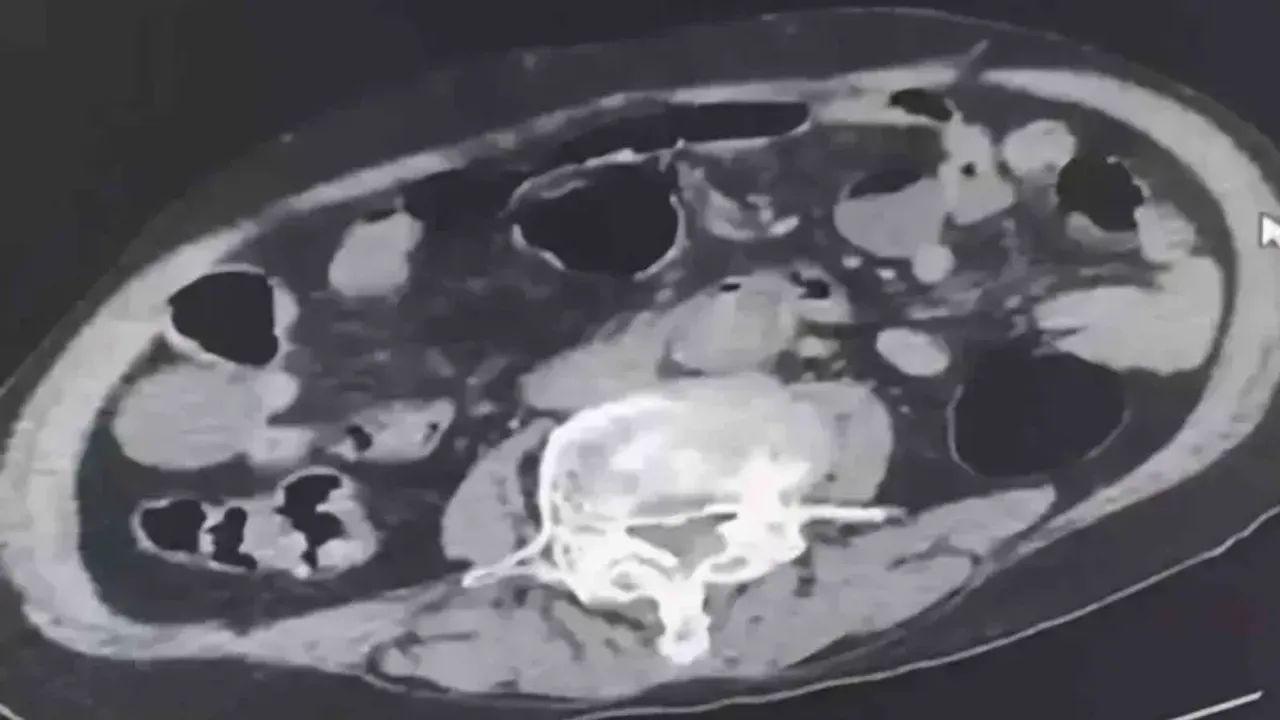

Denizli İl Emniyet Müdürlüğü Narkotik Suçlarla Mücadele Şube Müdürlüğü tarafından uyuşturucu madde ticaretinin önlenmesine yönelik yapılan çalışmalar kapsamında şehir dışından Denizli’ye uyuşturucu sokmak isteyen 2 yabancı uyruklu şahıs takibe takıldı. Takip sonrasında Denizli’de malları teslim edeceği kişi ile buluştukları esnada düzenlene operasyonla 3 şahıs gözaltına alındı. Gözaltına alınan şüpheliler üzerinde yapılan incelemelerde yabancı uyruklu bir şüphelinin uyuşturucu maddeyi cinsel organında taşıdığı belirlendi. Şüphelilerin üzerlerinde ve adreslerinden yapılan aramalarda 6 parça halinde 145 gram metamfetamin maddesi, 260 gram sıvı halde sentetik ecza maddesi ele geçirildi.